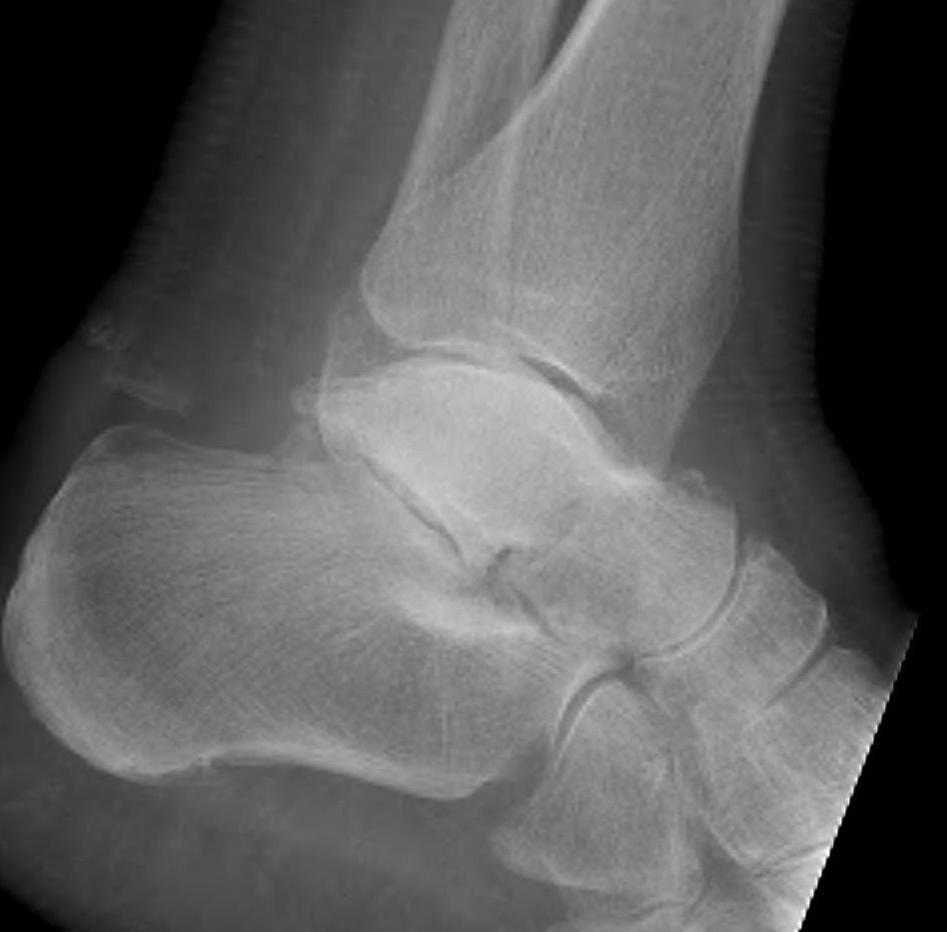

Hawkin's sign

Subchondral lucency under medial talar dome on xray

- appears 6 - 12 weeks post injury

- indicates vascularity

- presence excludes AVN